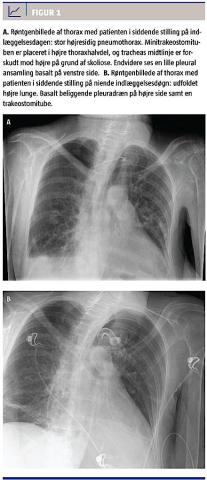

Endelig beskrivelse af røntgenoptagelsen af thorax, der blev taget ved indlæggelsen, inden patienten blev overflyttet til intensivafdelingen, forelå morgenen efter. Der blev konstateret en højresidig pneumothorax. Hun havde ikke tidligere haft pneumothorax. Ligeledes blev det noteret, at minitrakeostomituben var displaceret. På røntgenbilledet fremstod minitrakeostomituben ikke beliggende i trachea, men med et forløb over mod højre thoraxhalvdel (Figur 1 A). Der kunne aspireres luft på minitrakeostomituben, hvilket normalt er indikator for, at den er korrekt placeret. Ved løsning af minitrakeostomien kunne man se, at tuben var displaceret mod højre i stedet for at være placeret i midtlinjen over trachea. Det blev derfor antaget, at minitrakeostomituben var displaceret epitrakealt og havde perforeret højre pleura, hvilket havde forårsaget pneumothoraxen.

Årsagen til den respiratoriske insufficiens hos patienten i sygehistorien viste sig at være en højresidig pneumothorax. Ud fra fund ved røntgenoptagelse af thorax og konstatering af den displacerede minitrakeostomitube, er det overvejende sandsynligt, at der var tale om en senkomplikation i forbindelse med minitrakeostomianlæggelsen. På røntgenbilledet (Figur 1 A) ses det, at tracheas forløb var forskudt til venstre i forhold til midtlinjen. Det var ikke pga. en trykpneumothorax, men pga. patientens grundmorbus med skæv siddestilling og skoliose. Derfor fremstod minitrakeostomituben som beliggende i midtlinjen, hvor den faktiske placering var mod højre thoraxhalvdel. Røntgenbilledet af thorax efter trakeostomianlæggelsen viste samme venstreforskydning af trachea og trakealtuben beliggende i tracheas midtlinje (Figur 1 B). Der blev ikke foretaget en CT af den displacerede